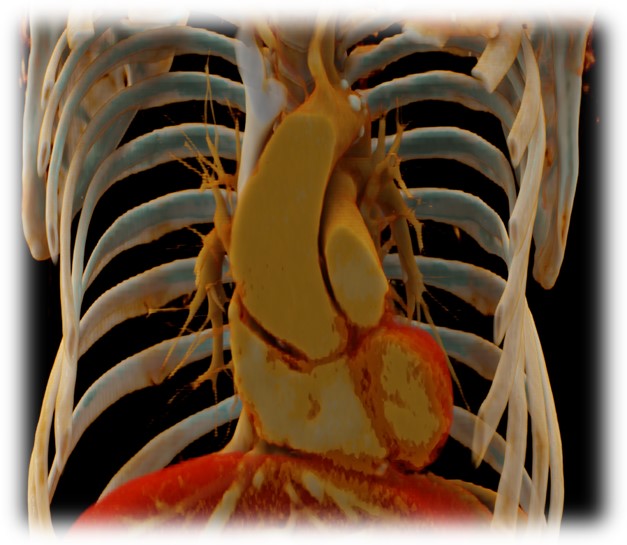

Pár kép az oktatás radiológiai részéről:

(SE-OKK, SIEMENS, CTISUS)